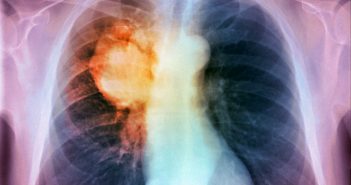

Tumori in aumento: 369mila nuovi casi nel 2017 in Italia Aumentano i casi di cancro…

Tumore ai polmoni: dal 2018 arriva un test italiano del sangue per la diagnosi del…